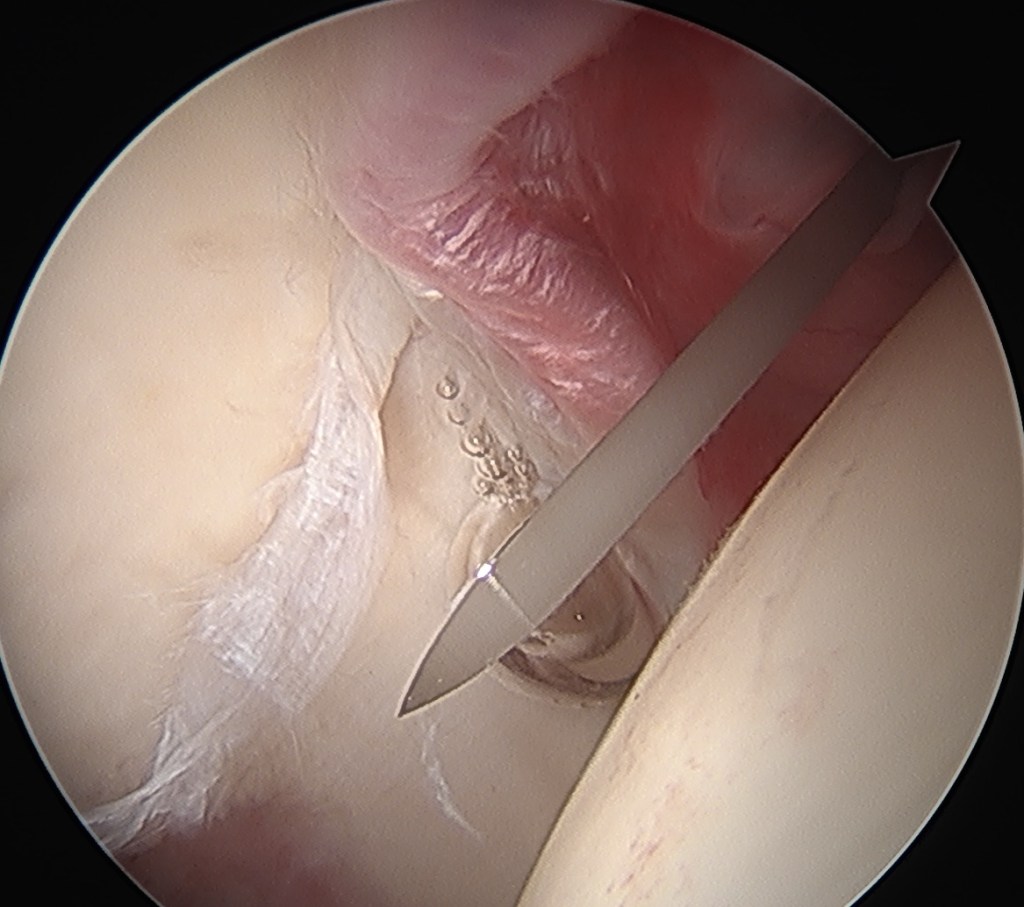

Dr Tim Dwyer is an orthopedic surgeon specializing in sports medicine and arthroscopy, performing surgery of the hip, knee and shoulder. Based at Women’s College and Mt Sinai Hospital, Dr Dwyer performs high volume ACL reconstruction, hip arthroscopy, rotator cuff repair, and operations for shoulder dislocation.

Dr Dwyer is an Associate Professor at the University of Toronto, responsible for training orthopedic fellows and residents in arthroscopy and sports medicine. Dr Dwyer is also active in research with over 100 publications in the fields of ACL reconstruction, rotator cuff repair, shoulder stabilization, and hip arthroscopy.